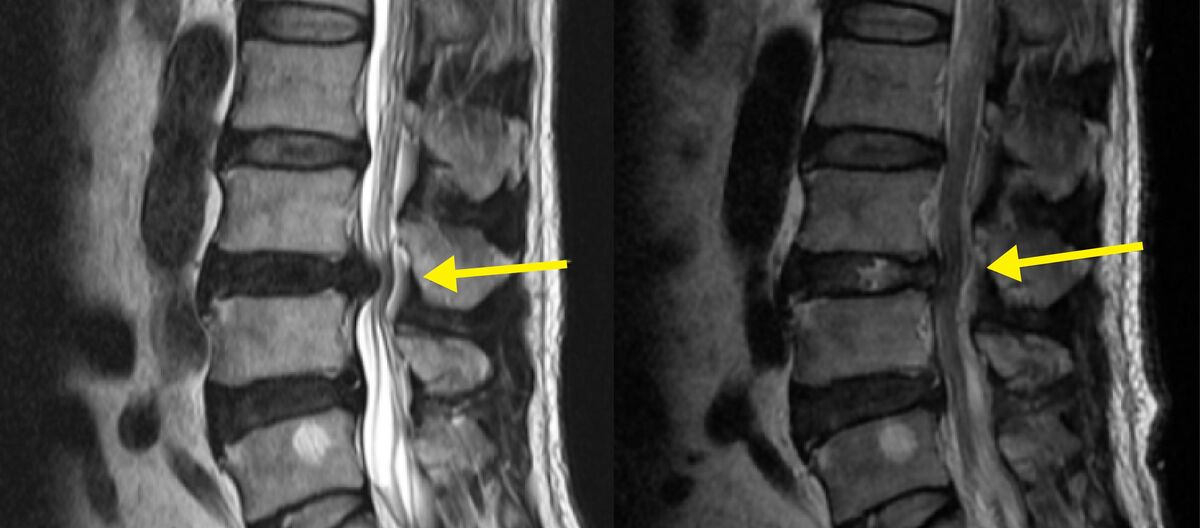

배장호 서울바른세상병원 신경외과 전문의는 “허리 디스크 초기에는 허리 통증만 느껴질 수 있지만, 진행되면 엉치나 허벅지, 종아리, 발끝까지 이어지는 방사통과 저림, 감각 저하가 나타난다. 반면 척추관 협착증은 신경이 지나가는 통로 자체가 좁아지면서 보행 시 다리가 터질 듯 아프고, 잠시 쉬면 호전되는 간헐적 파행이 특징”이라고 말한다.

이어 “통증 양상과 발생 상황이 다르기 때문에 정확한 감별 진단이 중요하다. 허리 디스크 치료의 기본은 단계적으로 접근하는 것”이라고 덧붙였다.

다만 통증이 지속적으로 악화되거나, 다리 힘이 빠지고 감각이 떨어지는 신경학적 증상이 나타나며, 대소변 장애나 하반신 마비 위험이 있는 경우에는 수술적 치료를 고려해야 한다. 중요한 것은 수술을 미루는 것이 아니라, 필요한 시기를 놓치지 않는 것이다.

최근에는 절개 범위를 최소화한 최소침습 디스크 제거술이 널리 시행되고 있다. 이 수술은 피부 절개를 크게 하지 않고, 작은 통로를 통해 내시경이나 미세현미경을 삽입해 신경을 압박하는 디스크 조각만 선택적으로 제거하는 방식이다.

국소 또는 부분 마취로 진행되는 경우가 많아 전신마취 부담이 적고, 근육 손상을 최소화할 수 있다. 수술 과정은 영상 장비로 병변 위치를 정확히 확인한 뒤 1cm 내외의 절개를 통해 기구를 삽입하고, 신경과 탈출된 디스크를 구분해 문제가 되는 부분만 제거하는 순서로 진행된다.